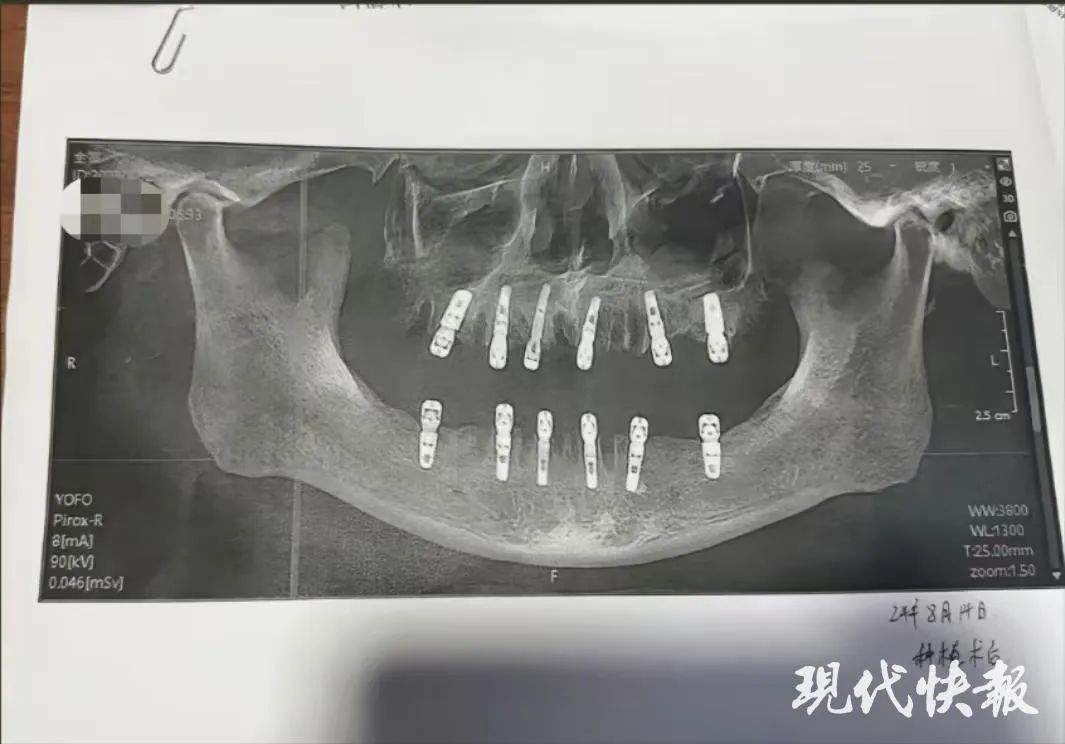

据舒女士发布的信息显示,其父亲黄某8月14日在德维口腔医院接受牙科手术。根据种植手术同意书显示,本次治疗拔牙23颗、种植牙齿12颗,并且均为即刻修复,即“当天拔、当天种”,负责进行治疗的医师为袁某。在结束种植牙手术后,黄某牙齿一直疼痛不止,并于8月28日因心脏骤停死亡。“没想到我爸走得那么快,给他买的新车都没来得及开。”舒女士说。